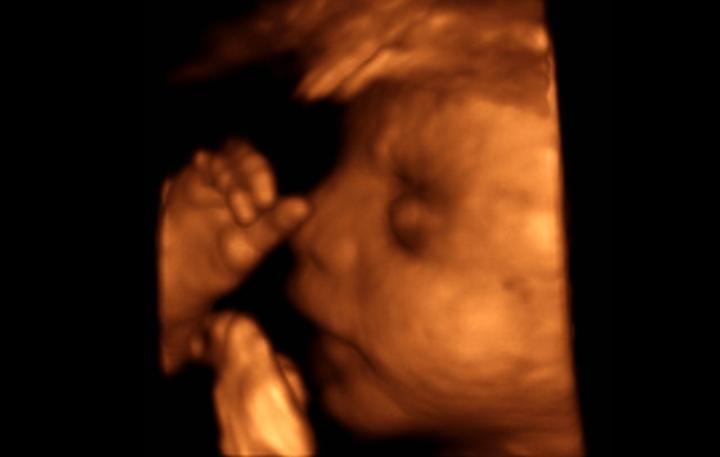

tak zítra nás čeká 3D ultrazvuk 🙂